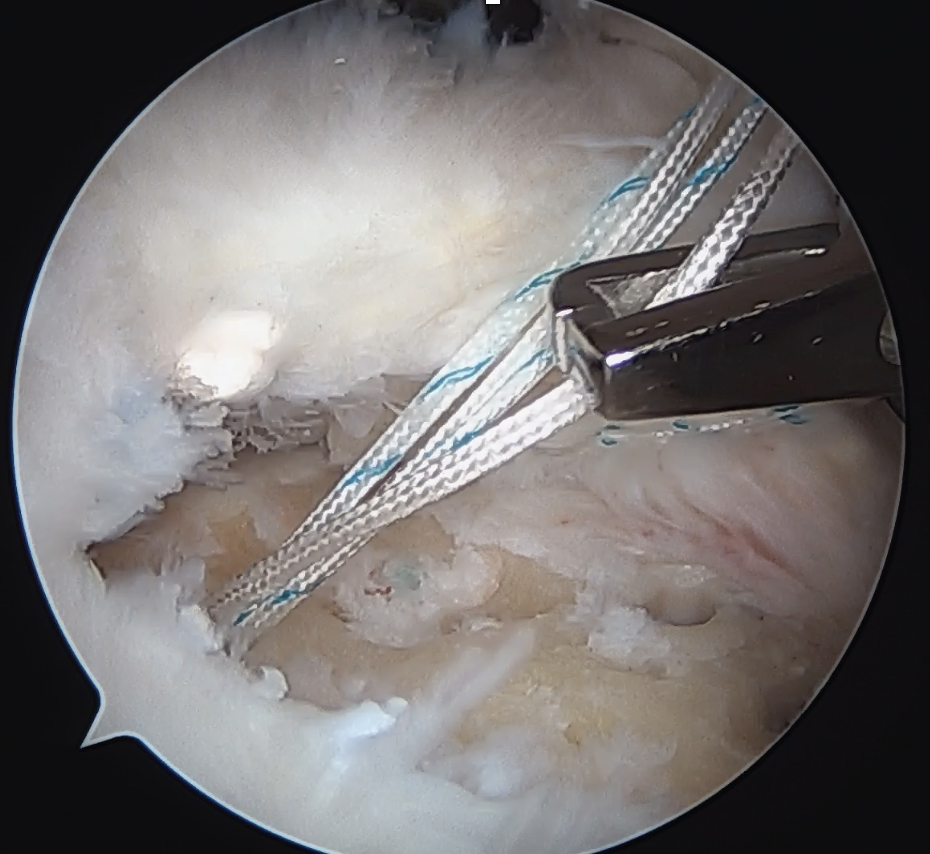

Trans-osseous equivalent / suture bridge

- cross sutures from medial row to lateral row

- increase contact between cuff and footprint

Double row / suture bridge

- use medial row sutures

- secure in knotless lateral row anchors